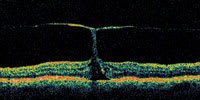

| Figure 4. A patient with an irregular shape to the fovea. This may represent a lamellar macular hole or a self-healed full-thickness macular hole. |

A central clinical challenge has been accurately diagnosing early macular holes which may be mimicked by many other conditions.34,35 No imaging modality has enhanced our diagnostic capability more than the OCT; superior imaging capabilities have improved diagnostic accuracy, clinical monitoring, and postoperative assessment.36-38 The OCT unequivocally demonstrates early stages of full-thickness macular holes (Figure 1), and allows distinction of pseudohole and pre-macular hole conditions in almost all instances. Fluid accumulation in early, presumed pre-macular hole stages have been corroborated by OCT observations (Figure 2). Serial images have been reported showing the progression from apparent impending macular holes to full thickness macular holes.39-42 It has depicted many other configurations that might be in the spectrum of lamellar or pre-macular hole conditions (Figure 3 and 4).